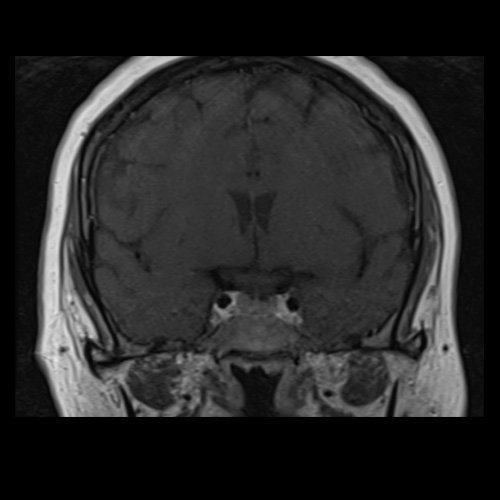

RMI de cráneo con contraste EV (21/02/26): Las cavidades ventriculares presentan tamaño y morfología normal. Las estructuras la línea media se hallan en su topografía habitual. A nivel de la fosa posterior el cuarto ventrículo se encuentra en línea media. Bulbo, protuberancia y mesencéfalo sin alteraciones. Relación sustancia gris blanca respetada. No se observan efectos expansivos. El examen de difusión no muestra alteraciones. El efecto FLAIR no muestra alteraciones. La secuencia SWI no muestra alteraciones. No se visualizan alteraciones en proyección, de la región selar, el quiasma óptico y senos cavernosos. No se observan realces patológicos tras la administración de gadolinio.

RMN de cráneo con contraste endovenoso (21/02/26) Corte sagital en secuencia T1: sin alteraciones en región selar.

RMN de cráneo con contraste endovenoso (21/02/26) Corte coronal en secuencia T1: sin alteraciones en región selar.

Tomografia de craneo con contraste endovenoso (10/02/2026) Corte axial: sin alteraciones a nivel selar.